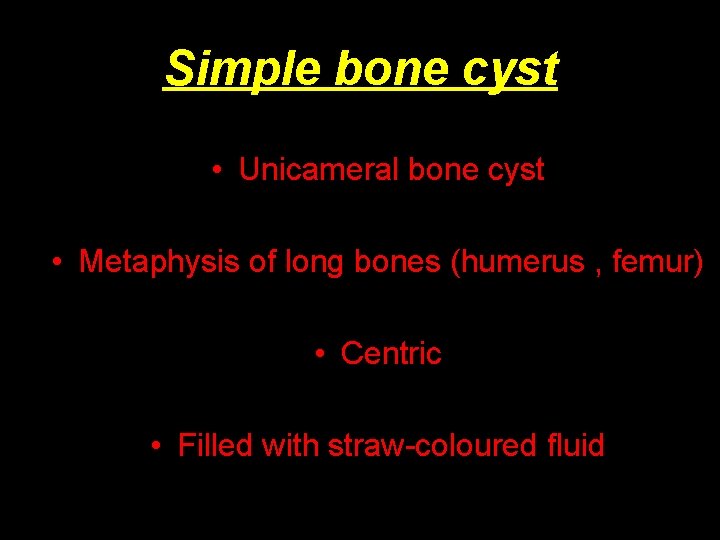

Simple bone cyst • Unicameral bone cyst • Metaphysis of long bones (humerus , femur) • Centric • Filled with straw-coloured fluid